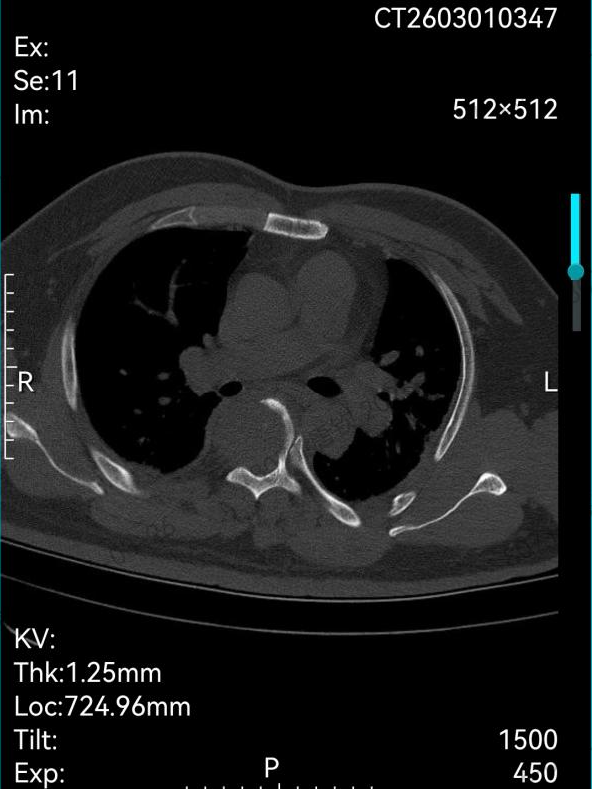

患者刘先生(化名)因顽固性胸背疼痛、渐进性呼吸困难,伴随双下肢进行性瘫痪入院,经详细检查确诊为第5胸椎侵袭性肿瘤。病灶位置极为特殊:椎体后方紧贴中枢脊髓,前方毗邻心脏、胸主动脉、气管、食管等关键脏器,解剖层次错综复杂、手术操作空间极度狭小,堪称外科手术的“雷区”。

术前影像检查图像